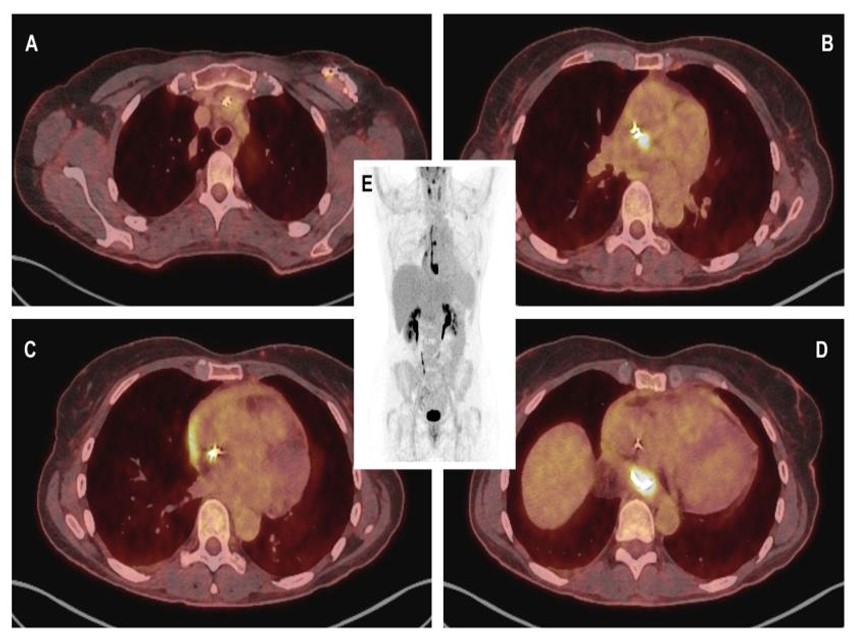

Fig. (3).

Fused CT-PET with 18F-FDG images (A) showing slight metabolic activity at the lead exit point, with more intense uptake from the entrance into the innominate vein extending to its distal end; (B) exhibiting greater focality in the middle third; and (D) demonstrating the region of the paraesophageal pericardial abscess, with a maximum standardized uptake value (SUVmax) of 16. (C) A thin line of activity was observed in the pericardial effusion, more intense in the region adjacent to the right atrium. (E) Volumetric PET reconstruction demonstrates the previously described findings.

Positron emission tomography with 18F-fluorodeoxyglucose (18F-FDG PET) was performed, which confirmed the suspected diagnosis, demonstrating infection of the generator and leads with involvement of the atrial wall and formation of a pericardial abscess (Fig. 3A-E). Both multiplex FilmArray testing and blood cultures remained negative after 14 days.

If, as in this case, there are no external signs of infection in the generator or microbiological isolation, 18F-FDG CT-PET scanning is recommended by international guidelines as the ideal and most sensitive tool for identifying CIEDI. It is also useful for detecting potential primary sources of infection or distant infectious embolisms [11, 12].